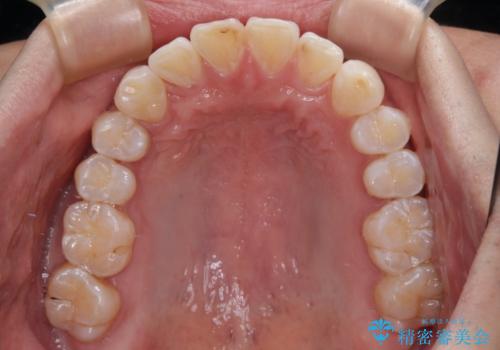

- 以前矯正治療を行ったものの、思い通りの仕上がりではなく、更には後戻りが気になってきたとのことで来院された患者様です。

上顎右側の第一小臼歯が動きにくい歯であり、以前矯正治療を行った際に傾斜した位置のまま終了したことと、それに伴い後戻りで歯列が波打っているようになっていることを大変気にしていらっしゃいました。

咬合平面改善のため、アンカースクリューを多用し、ワイヤー装置にて矯正治療を行うこととしました。

動きにくい歯はやはり動きにくく、咬み合わせ改善に時間を要しましたが、患者様には大変満足していただけました。